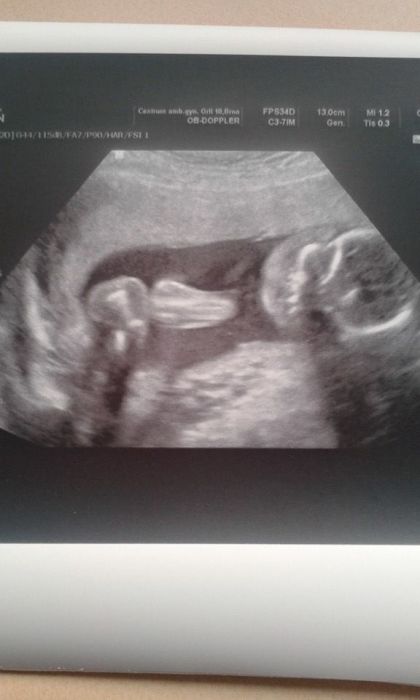

Dnesni poradna za nami.Broucek necekane spinkal,takze jsme na utz kozkaly s pani Dr jak ziva

Jinak vse v poradne,srdicko krasne tluce a potvrzen chlapecek (jen na utz to bylo lepe videt nez na fotecce).Navic neni asi fotogenicky,takze ani jedna fotecka neni nic extra.Placentu mam vepredu,proto citim tak malo a slabe prdolku.S vahou jsme se dostali na vychozi vahu,takze k dnesku +0kg.Velky utz nechan tedy na 17.3. a dalsi poradna 3.4. takze ted uvidim Filipka kazdych 14 dni

Přikládám fotečky